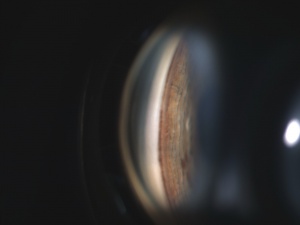

Though commonly seen with PDS, a Krukenberg spindle (Image 2) in and of itself is not necessarily pathognomonic of the disease, as it can also be found with pseudoexfoliation syndrome. Distribution of pigmentation in the trabecular meshwork can help differentiate PDS from pseudoexfoliation syndrome, with homogenous distribution associated with PDS and patchy distribution with pseudoexfoliation syndrome. Pigmentary glaucoma is considered present when the criteria for PDS are accompanied by optic nerve cupping and/or visual field loss.[40]

Patients with suspected PDS or PG should undergo gonioscopy prior to dilation to document the extent of trabecular pigmentation (Image 4). The angle is typically widely open, and the trabecular meshwork typically shows dense, homogenous pigmentation.[23] Pigment deposition may be noted on Schwalbe’s line. The peripheral concavity of the iris may be more prominently appreciated on gonioscopy. Pigment deposition along the zonular attachment at the posterior capsule of lens may also be noted (Schie line or Zentmayer line), which can give rise to a pigmented round line at the posterior capsule just internal to the equator of the lens.